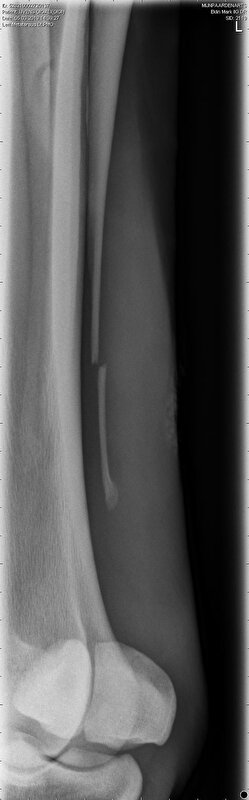

Hierbij de foto's degene die ik naast elkaar gezet heb is links van 5 maart en rechts van 29 maart.

Links dus 5 mrt en rechts 29 mrt

Daar mijn DA nu dus zegt dat het wel aan elkaar kan groeien weer alleen moet je voor boswoekering waken en dat zag ze nu niet. Dat is de reden dat ik nog niet heb geopereerd. Maar ja ik twijfel er zelf een beetje aan maar ben geen dierenarts. Je ziet op de foto's dat het wel al meer naar elkaar toe komt en op rechter foto zie je ook in een hoekje al vaag iets groeien. Dus ja dat zie ik ook en zag op ook een foto van een breuk die verder weg stond maar wel genezen is dus het zal wel kunnen lijkt me.